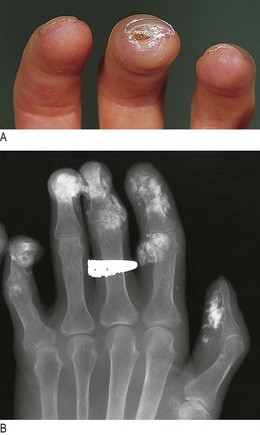

In systemic sclerosis, the thickened, tight skin produces a characteristic facial appearance (Fig. 3.11C). In the hands, flexion contractures, calcium deposits in the finger pulps (Fig. 14.9) and tissue ischaemia leading to ulceration may occur. The telangiectasias of systemic sclerosis are purplish, blanch with pressure and are most common on the hands and face.

Fig. 14.9 Systemic sclerosis in the hand. (A) Calcium deposits ulcerating through the skin. (B) X-ray showing calcium deposits.